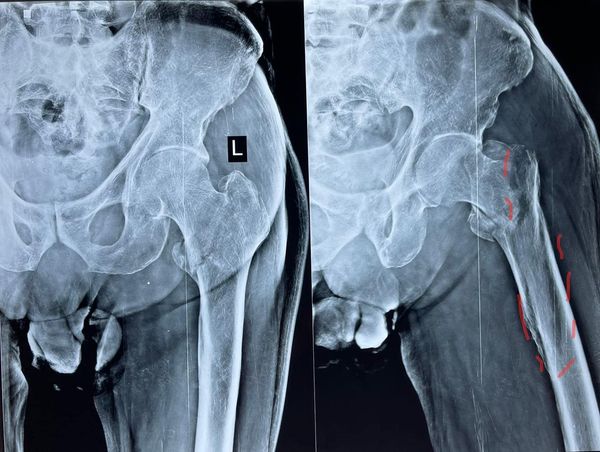

68 year old man ACL (anterior cruciate ligament) reconstruction of Knee

There used to be a common consensus that ACL reconstruction of knee should not be done in old age, this idea has now largely been debunked with statistical evidence. this 68 year old man with a traumatic anterior cruciate ligament tear had intact lateral and medial meniscus and quite normal cartilage in the weight bearing […]